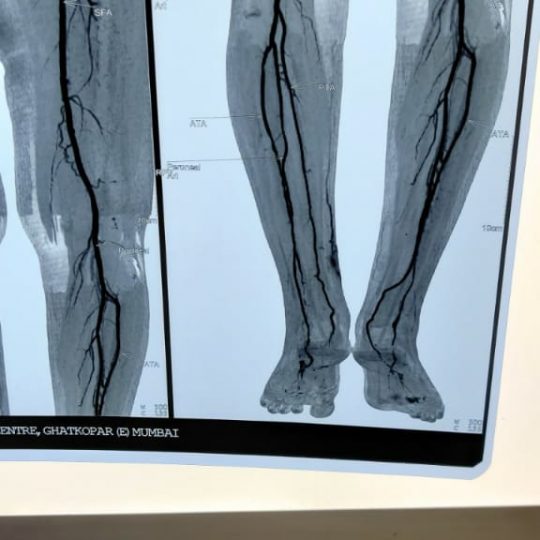

Patient’s Successfully Treated with Diabetic Foot Problems